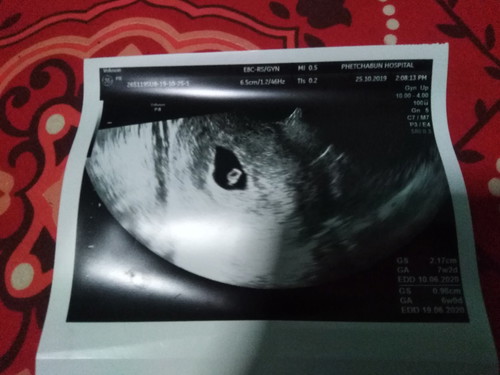

กังวลมากค่ะ เลือดไหลมา2วันแล้วแต่เราไปหาหมอมาแล้วค่ะ กลัวจะแท้งคุกคามมากเลยเราะควรทำไงบ้างค่ะ 6w